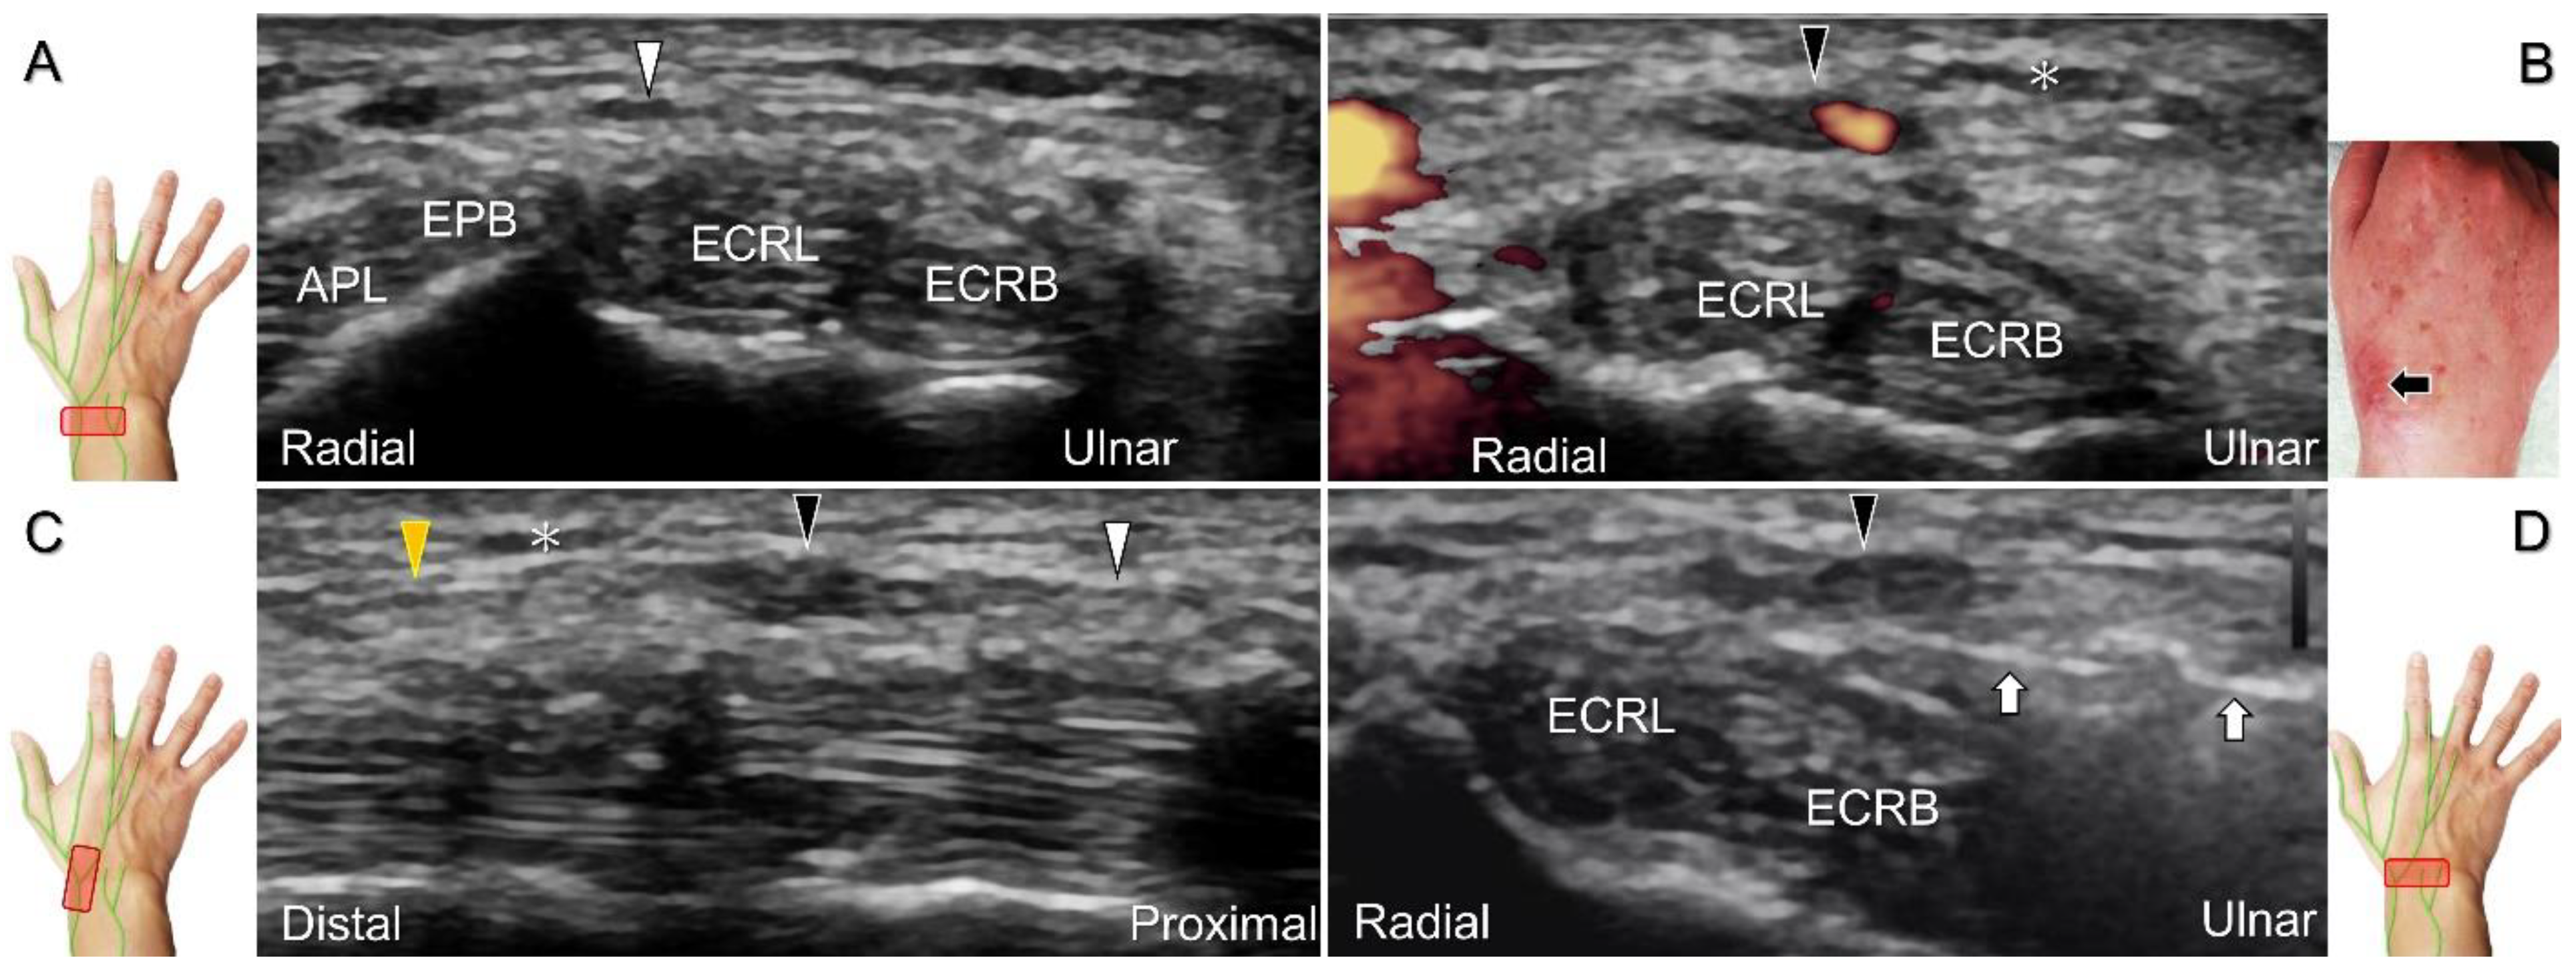

Figure 24. Sonographic imaging of the superficial radial nerve entrapment due to a post-surgical scar. Short-axis imaging at the normal (A) and the swollen (B) segment proximal to the entrapment. The normal, swollen, and entrapped segments of the nerve are seen in long-axis view (C). Ultrasound-guided hydrodissection of the nerve from the ulnar aspect (D). White arrowheads: normal segment; black arrowheads: swollen segment; orange arrowhead: entrapped segment; white arrows: needle; black arrow: scars on the skin; asterisk: scars in the subcutaneous tissue; APL: abductor pollicis longus tendon; EPB: extensor pollicis brevis tendon; ECRL: extensor carpi radialis longus tendon; ECRB: extensor carpi radialis brevis tendon.

Cheiralgia paresthetica, also known as Wartenberg’s syndrome, is the compressive neuropathy of the superficial radial nerve. Symptoms such as tenderness, numbness, and allodynia can be exacerbated by wrist flexion and ulnar deviation. The nerve can be compressed by a handcuff, watch, bracelet, metal implant, ganglion cyst, or distal radius fracture. Nerve entrapment commonly takes place at the proximal intersection zone pertaining to the first and second extensor compartments (Figure 22).

Additionally, acupuncture and cannulation of the cephalic vein over the distal forearm can lead to nerve injury. To prevent iatrogenic injury, the superficial radial nerve before injection should also be recognized for de Quervain’s syndrome (Figure 23A) [44], ganglion cyst aspiration (Figure 23B), and catheterization (Figure 24A–C). For injection of the superficial radial nerve, an in-plane approach in the nerve’s short axis is preferred (Figure 24D).

For those receiving surgery such as fixation or debridement of the radial wrist, the nerve can be occasionally injured, resulting in residual numbness, allodynia, dysesthesia, or hypoesthesia (Figure 25).

Figure 25. Sonographic images depict the location of a neuroma of the superficial radial nerve. The normal/proximal segment (A) and the neuroma in short-axis (B) and long-axis (C) views are seen. White arrowhead: superficial radial nerve; black arrowheads: neuroma; APL: abductor pollicis longus tendon; EPB: extensor pollicis brevis tendon; ECRL: extensor carpi radialis longus tendon; C: cephalic vein.